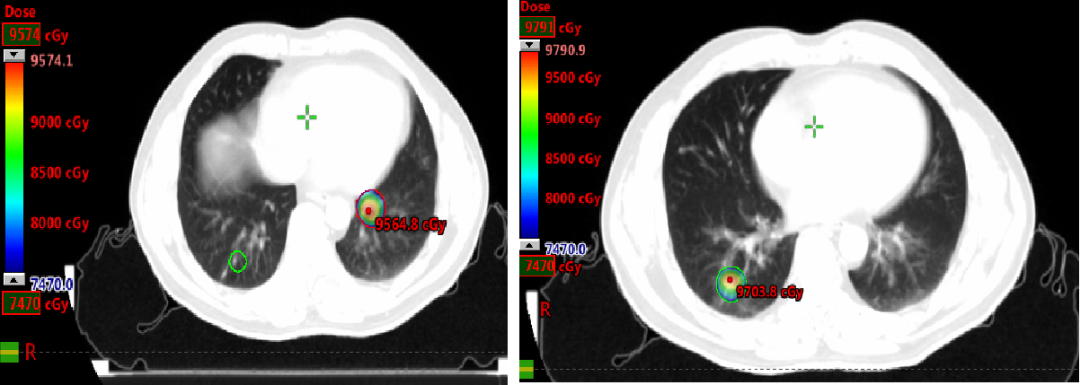

局部治疗(二):SBRT治疗

2020-11-6至2020-11-25 左肺下叶及右肺下叶转移灶放疗:95% PTV1-2 74.7Gy/4.98Gy/15F。

2020-12-31至2021-1-19右肺上叶转移灶放疗:95% PTV 74.7Gy/4.98Gy/15F。

SBRT疗效评价:部分缩小。